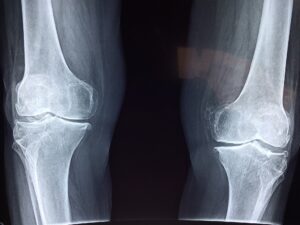

Twoje kolano boli, jest opuchnięte, a może zbiera się tam woda? Bez obaw, istnieją sprawdzone, domowe sposoby, które pomogą w tego typu dolegliwościach!

Oto lista domowych metod pomagających w bólach i obrzękach kolan: